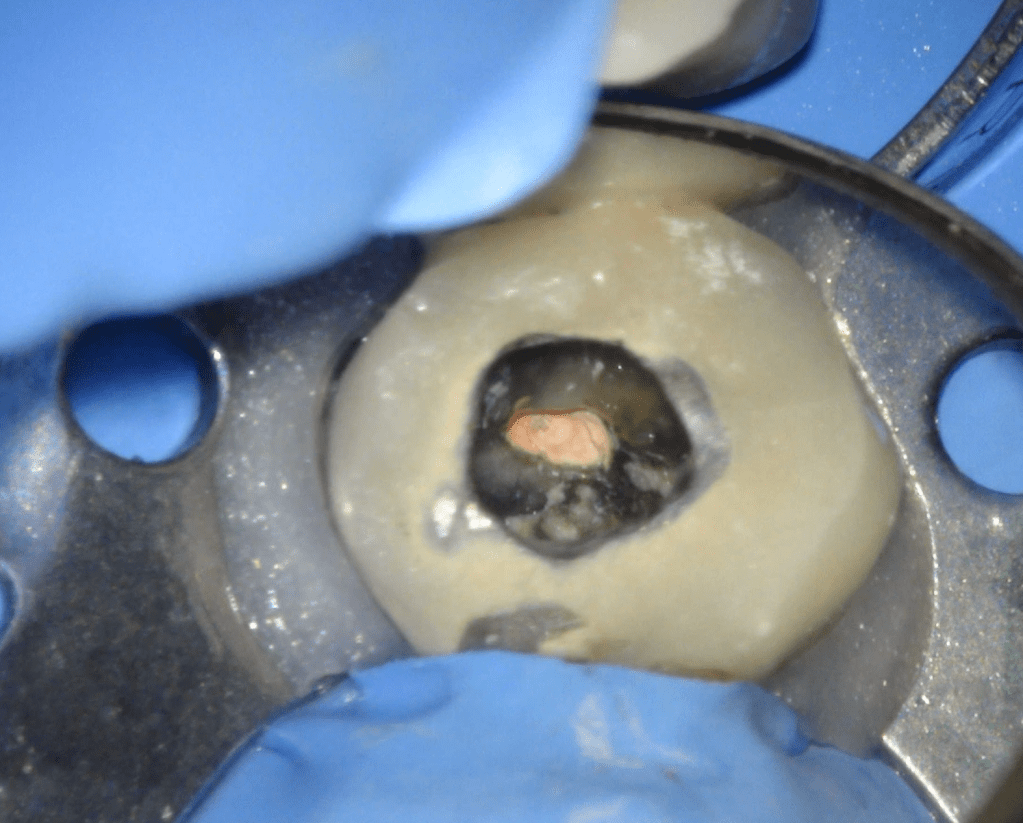

Reco pared vesticular